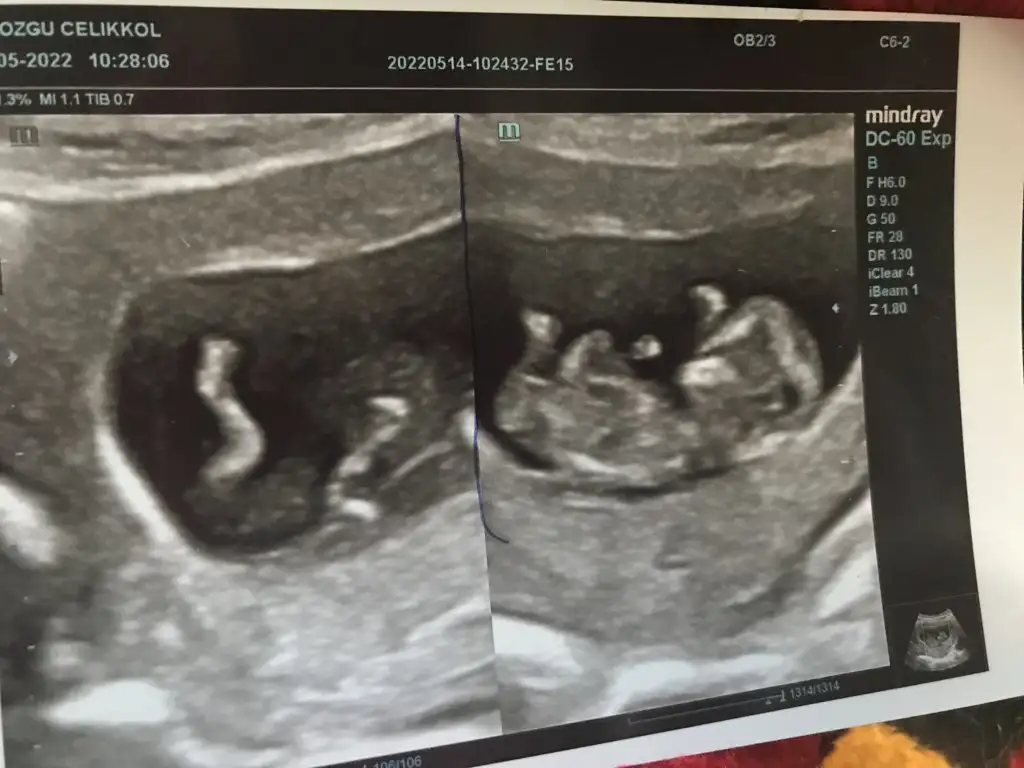

paşacık geliyorCinsiyet tahmin eder misiniz bu konuda tecrübeli bilen arkadaşlar yardımınızı rica ediyorım 10+6 yız bu resimlerde

Tahmin dogru cikti doktorum 13. Haftada erkek dedi. Tesekkur ederimmmpaşa gibi

bir annemize yapılan yorum daha tuttuTahmin dogru cikti doktorum 13. Haftada erkek dedi. Tesekkur ederimmm